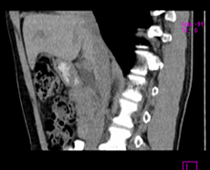

患者,男,57,常年不吃午饭,近一个月来腹部隐痛,无明显黄疸,明天进行增强扫描,图象另上传,麻烦各位帮忙一起看看讨论讨论

肝外胆管扩张,胰头增大,肠系膜上静脉似有包埋征象。

考虑:胰头占位性病变,建议增强进一步检查。

肝外胆管稍扩张,胰腺钩突略增大,但外形尚可,境界清楚。(常年不吃午饭)提示胰腺炎可能大,肿瘤第二步考虑。

支持考胰头占位性病变,感觉十二指肠壁不规则增厚,不排除十二指肠降部占位可炎症

胰头增大,胆总管增宽,考虑胰头癌可能性大,明天看增强片有助诊断.